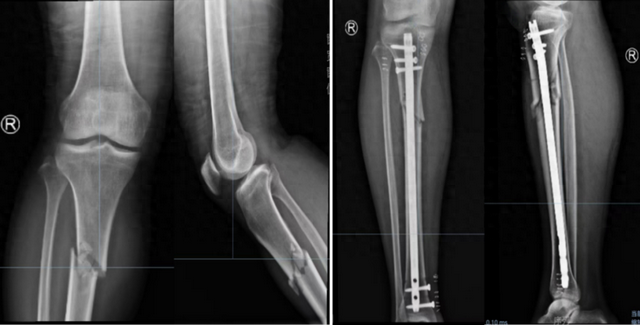

胫骨干骨折髓内钉固定

胫腓骨多端骨折胫骨髓内钉+腓骨弹性髓内钉固定